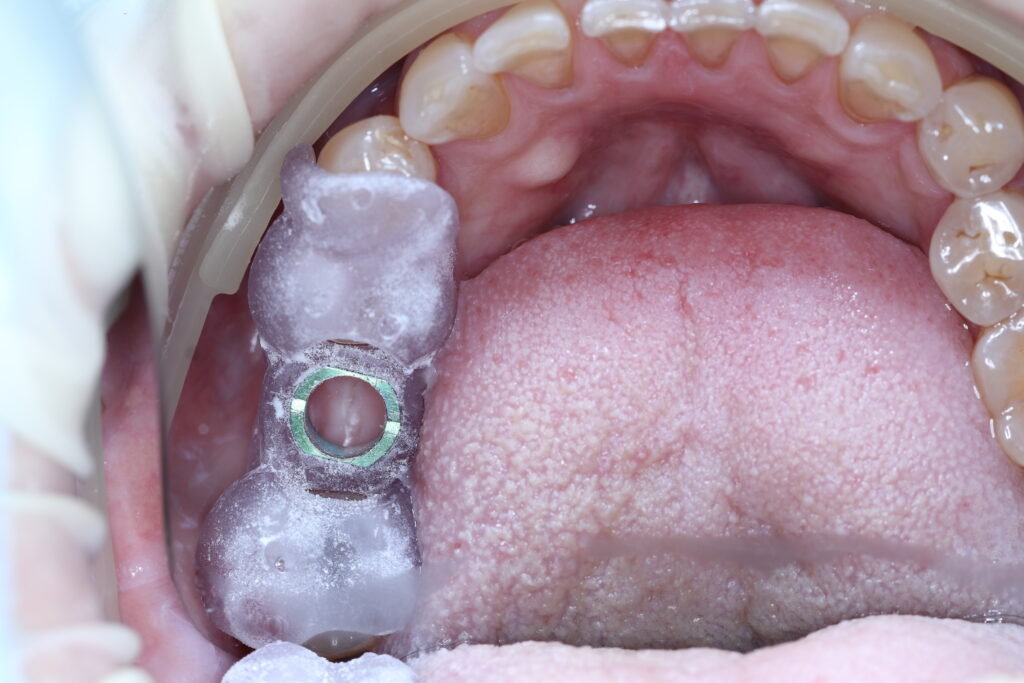

ผลงานบางส่วน ของทีมทันตแพทย์ของคลินิกเรา โดยได้รับอนุญาตให้เผยแพร่ ด้วยความเต็มใจจากผู้ป่วยขอบขอบคุณผู้ป่วยทุกๆท่าน

ตัวนำรากเทียมระบบดิจิทัล

การรักษารากฟันเทียมแบบดิจิทัล ที่ช่วยให้ทันตแพทย์สามารถวางแผนตำปหน่งรากฟันเทียมได้ตามความต้องการ โดยขึ้นอยู่กับความต้องการในการบูรณะรากฟันเทียม และเงื่อนไขของการผ่าตัด